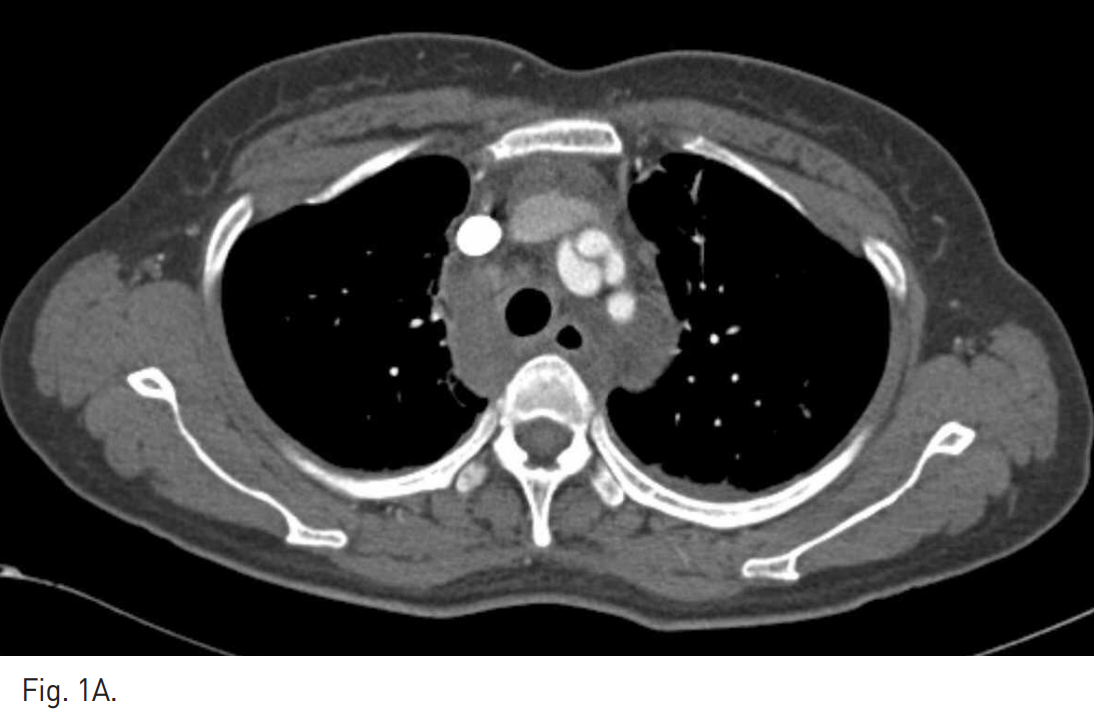

Fig. 1

A, B. Arterial phase axial (A) and coronal MIP (B) images of chest CT scan show the dissection with pseudoaneurysm formation at the right brachiocephalic trunk. Small amount of mediastinal hematoma is noted.

흉부 CT에서 aortic arch에서 약 0.5cm 떨어진 right brachiocephalic trunk에 약 2.7cm 길이의 dissection이 관찰되며 약 1.6cm의 pseudoa neurysm이 동반되어 있다. 또한 주위 종격동에 혈종이 있다(Fig. 1A, B). Supine position에서 시행한 복부대동맥조영술에서도 right brachiocephalic trunk의 dissection과 pseudoaneurysm이 잘 관찰된다(Fig.2A). Wire와 catheter를 이용하여 병변 부위를 통과한 후, covered stent를 설치하였다(Fig. 2B). 2주 후 시행한 추적 흉부 CT상 dissection과 pseudoa neurysm은 더 이상 보이지 않았다(Fig. 3A, B).